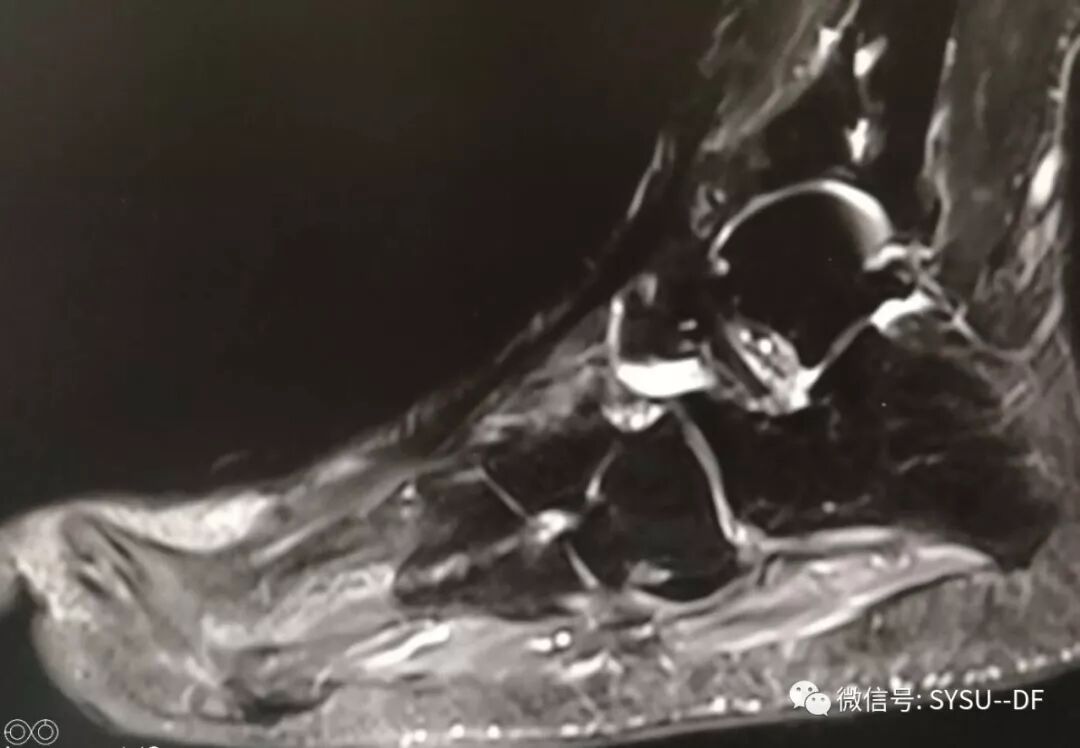

但从MR的结果来看,在重重叠叠的不规律的纤维组织中,还是有一些空腔,目前没有明确的炎症反应,还有些趾骨和跖骨,还是有一些炎症,目前没有更多的方法去解决这些问题。还是等伤口完全愈合后,继续观察吧。希望这些横七竖八的纤维能够把最后残留的细菌阻挡住,希望人体抵抗力能够最终消灭这些“穷寇”。